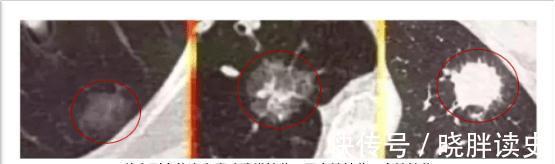

2. 看结构

实性结节:完全是一个高密度的影子,在CT下呈现白色的。实性结节,表面光滑小而圆的,多属于良性。直径大于0.8厘米有恶性特征的实性结节,比如恶性结节有分叶、毛刺、中间有空泡,有些会有胸膜牵拉,也可能会往正常的肺组织里伸展扩散,吸取周围组织的营养让自己迅速生长,可以说是“最可怕的结节”。当不好拿主意时,有条件的可以做PET-CT,可以看肿瘤葡萄糖代谢,代谢增高的肿瘤可能大。

纯粹的磨玻璃结节:类似磨砂玻璃表面一样,结节体积小于0.8厘米,边界较清楚,多属良性。但磨玻璃结节恶变,易形成肺腺癌,且高发于女性。

部分磨玻璃样结节:也叫亚实性结节,顾名思义就是具备以上两种特征表现的结节,通常为磨玻璃表现中间夹着部分实变的结节,恶性率在60%以上。